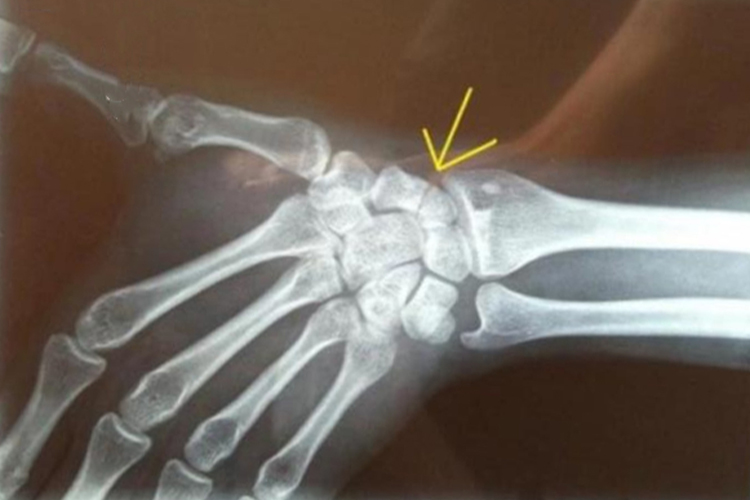

手腕骨折主要表现为伤后局部疼痛、肿胀,腕关节活动功能障碍,严重时可造成畸形。一般可通过X线检查,即腕部正位、侧位和尺偏斜位等进行明确诊断。

手腕骨折对于新鲜的无移位骨折、侧方移位幅度小于1mm或结节部的稳定骨折,以管型石膏或塑形硬纸壳固定,通常可获得良好的愈合。对于侧方移位幅度超过1mm,舟月交角大于60°的不稳定骨折及陈旧性骨折,以切开复位外固定为宜,具体可在医生指导下进行判断。